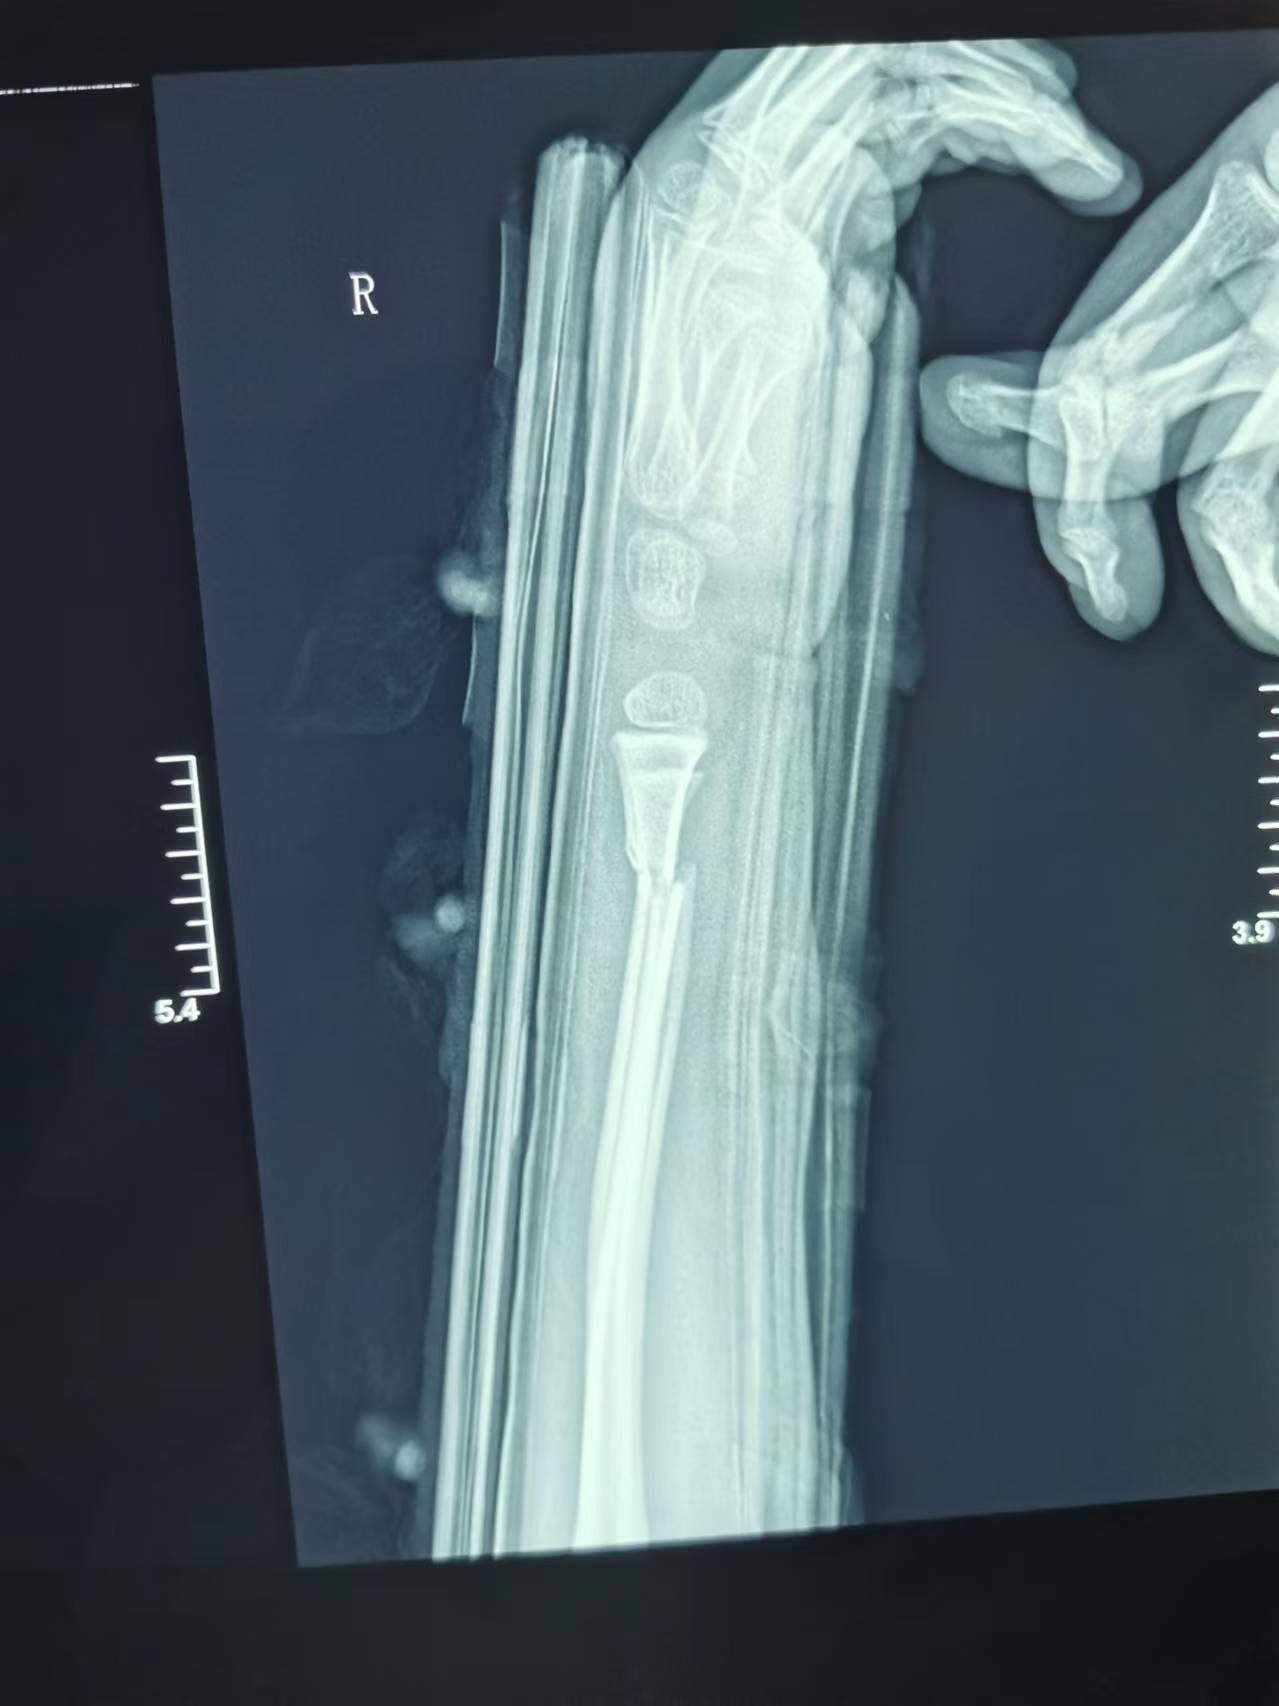

首页 > 张恒云工作室 > 影像资料 一